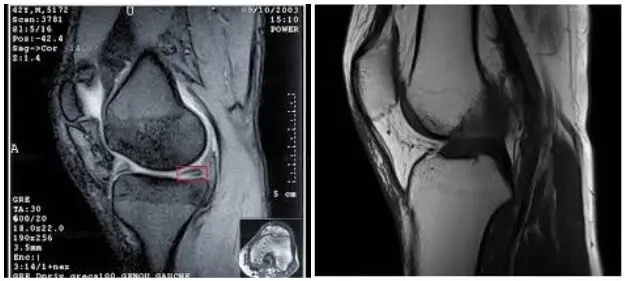

МРТ коліна дозволяє бачити тонкощі і особливості ушкодження тканини коліна, наприклад при травмі (меніски, зв’язки, скриті переломи кісток і багато іншого).

МРТ колінного суглоба (фото 1)

Артрит колінного суглоба, кіста Бейкера (МРТ).